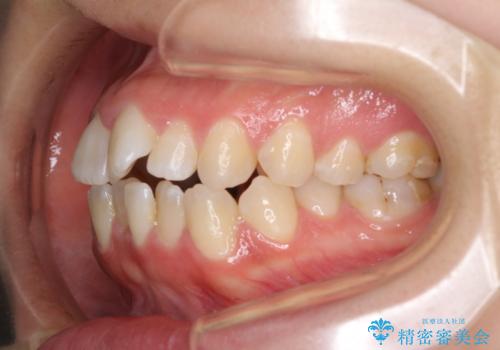

- 前歯の上下スペースによる食べにくさを気にして来院された患者様です。

インビザラインにより上下の前歯の隙間を閉じていくこととしました。

前歯のデコボコの解消と並行して上下の奥歯を圧下させるようにすることで、前歯を接触させるように計画しました。

上下の隙間に舌が入り込むことがオープンバイトの原因であったため、舌の筋肉のトレーニングも並行して行い、後戻りの抑制を図りました。